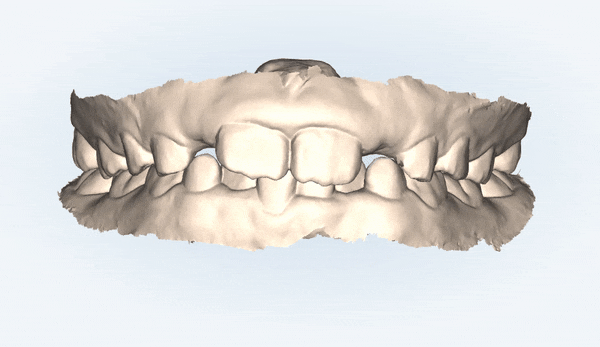

먼저 닥터킴의 정밀한 진단을 위해

i-TERO 로 구강내 스캔을 해보았습니다.

위 사진은 접촉되는 치아면을

spot 으로 표시해 확인해 볼수 있는데요,

노란원 안의 찍힌 spot들을 보니

아랫니가

윗니의 치아면이 아닌 입천장에 닿고 있었습니다.

아래 앞니의 잇몸 퇴축도 진행되고 있는 상황이었어요 ㅜ

유펜바른치과의

정밀진단 결과

치아가 너무 깊게 물리는 과개교합

상태였습니다.

과개교합은

윗니가 아랫니를 비정상적으로 깊게 덮고 있어

아랫니가 잘 보이지 않고

어린 나이에도 불구하고

아래 치아에 마모가 관찰되는 것이 특징입니다.